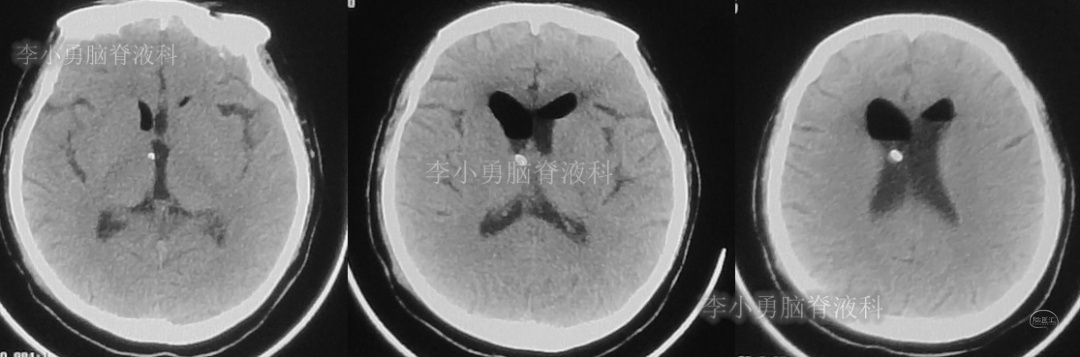

此次分流泵调压后1个月,即2018年12月11日,患者第3次出现头痛,而且头痛逐渐加重并昏迷,急到当地的第1家医院行头颅CT(图-7)见脑室从缩小又变成扩大状态。

图-7:2018年12月11日头颅CT

第3次调压后18天,即2018年12月29日,患者恢复好,在当地第1家医院复查头CT(图-8)见脑室明显缩小。

图-8:2018年12月29日头颅CT